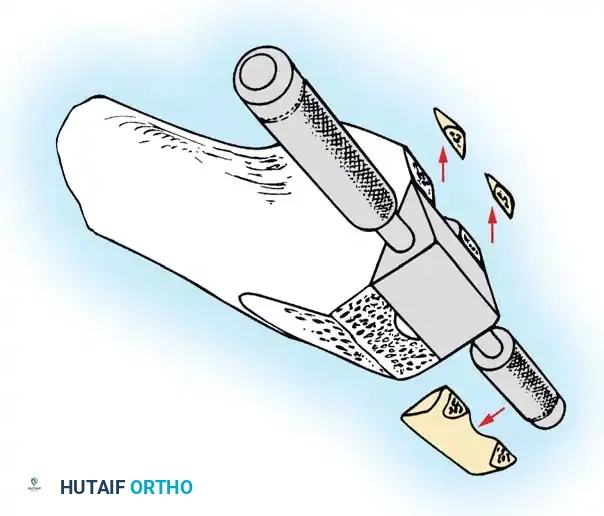

Femoral Chamfer Cuts and Intercondylar Preparation

Once sizing and rotation are established, the cutting block is pinned in place.

- Complete the distal femoral preparation by making the anterior, posterior, and chamfer cuts.

- If a PCL-retaining (CR) prosthesis is used, the intercondylar notch is left intact.

- If a PCL-substituting (PS) design is chosen, an intercondylar box cut is performed to accommodate the housing for the post-and-cam mechanism.